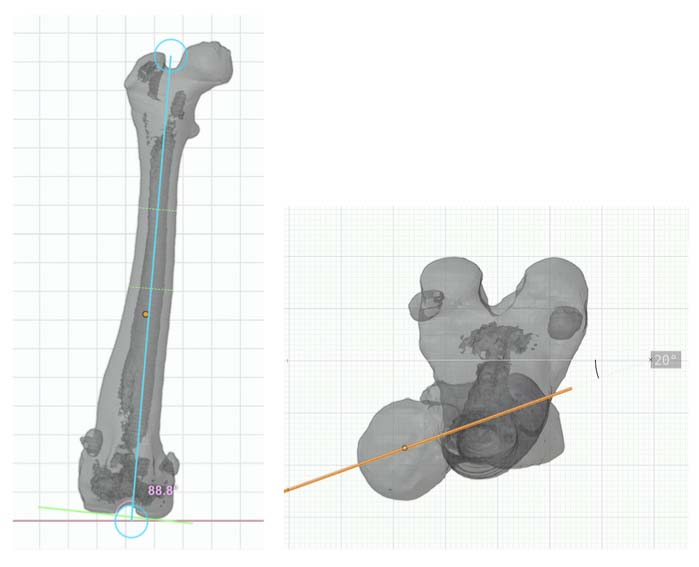

A method of planning and correction, commonly used in human surgery, has been adapted for the small-animal patient. This method is called the center of rotation of angulation (CORA). With this method, bone axes and joint orientation angles were made to provide guidance for accurate correction of angular limb deformities based on one standard set of geometric principles as they apply to osteotomies, regardless of the bone in question or the type of fixation device.

CT CAD-based approach to deformity planning documented two right femoral deformities:

Excessive anatomical lateral distal femoral angle (aLDFA) = 88.8 degrees

Femoral version 20 degrees

One right tibial deformity (19 degrees of excessive tibial internal torsion)

CT CAD-based surgical plan.